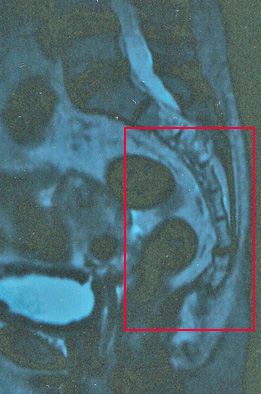

昨日、コキンの緩和ケア外来と整形外科の診察日で病院へいってきた。1週間前にMRI検査を済ませていたので、その結果も気になっていた。緩和ケア外来は、病院内に新設されたばかりで、認定看護師さんが、優しくコキンの最近の痛みの状況を、時間をかけて聞きだしながら、気持ちをユッタリとさせてくれる。同伴しているカチンの悩みまで受け入れてくれる。さすが、命の末期を迎える患者やその家族に接する、難しい看護を学び、実践されている看護師さんと、頭が下がる。でもコキンは、余命何日という病気ではない。例の少ない「脊索腫」という仙骨の腫瘍の痛みに、長く耐えてきたのだが、段々と増す激痛から、逃げ出したいと排便排尿機能を喪失する事を承知の上で、仙骨切除の大手術を受けたのだった。結果論だが、この手術の選択は間違いではなかったのだろうかと、今もこれからもコキンの今のQOLを考えると悩んで苦しんでいくであろうと思う。今まで、何回も書いているが、確かに痛みの原因であった部位は切除したのでその部位に痛みは無い、というより神経の切断により、肛門は全く無神経で、冷たい熱いすら感じなくなり、排便介助でトイレでウオッシュレットでおしり洗浄やビデを使っても、お湯が当たっていることさえ感じない、本当に涙しながら介助している毎日である。勿論、正確な便意も尿意もなく時間で動作している。上のMRI画像は、昨年秋のものである。枠で囲んだ仙骨がなくなったお尻は昔、美形だった可愛いお尻を、ペコンとへこませてしまった。まあ、カチンとコキンは手術前からこの程度は覚悟もしていたのだが、仙骨上部で切断された神経が術後、大暴れしているのでこの痛みが、術前と場所こそ変われ、痛みはより激しく、腰からつま先まで、針でさすような痛みの毎日なのである。痛みを抑える為、使っていたデュロテップMTパッチは、眠り続け意識まで朦朧とさせるので、停止して辛抱させているのだが、レスキューのオキノームの副作用は頑固な便秘となり、どうしてやればと考え込む。 そんな生活の中で、介護するカチンが大分慣れてきた事で、現状の中で二人の楽しみと希望を少しづつ見出せてきた。コキンも杖で隣の元気村まで歩けるようになってきた。車に乗せれば、1時間位なら大丈夫、休憩しながらゆっくり行動すれば旅行も行けるだろう。家の中では歩行器も要らない。トイレにも浴室にも移動できる。バリアフリーの家と周囲の環境に恵まれ、ユックリ、ユッタリ生きていく術もぼつぼつ見えてきた。昨年元気だったコキンが植えたブルーベリーにも実がなり、コガネムシがデートにやってきた。朝6時半、洗濯から始まる主夫業も、夜10時コキンに「マイスリーとデパス」を飲ませて終わる介護生活を「受けるコキンの辛さ」を思えば、71歳のカチンが1歳のコキンに愛を持ち、いとおしく育てるんだと考えよう。